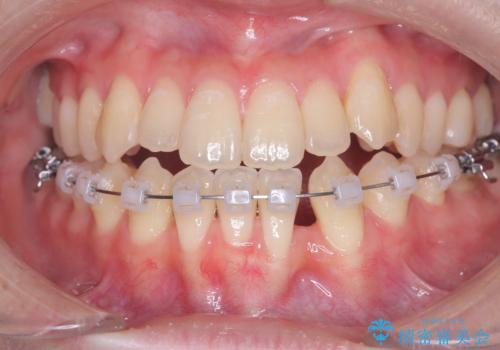

診査の結果、すでに下顎前歯の抜歯が行われていましたが、マウスピースの適合が著しく悪くなっており、歯が計画通りに動いていない状態でした。また、歯を支える骨の厚みや歯肉の薄さを考慮すると、このままマウスピースによる傾斜移動を続けるのは歯肉退縮(歯茎が下がること)のリスクが非常に高いと判断。

安全かつ確実に抜歯スペースを閉じ、咬み合わせを完成させるため、マウスピースから**ワイヤー矯正(マルチブラケット装置)**へ切り替えるリカバリープランを提案しました。

装置の変更と歯肉への配慮: ワイヤー矯正は歯の根(歯根)を平行に移動させる「歯体移動」を得意としています。本症例では、歯肉退縮を防ぐために、歯の傾きを精密にコントロールしながら抜歯スペースを閉じる必要がありました。ワイヤー装置を用いることで、インビザラインでは難しくなっていた三次元的な細かい調整を可能にしました。

リカバリーのプロセス: 適合が悪くなったインビザラインを一旦中止し、ブラケットを装着。停滞していた歯の移動を再開させ、上下の正中(中心)や奥歯の咬み合わせを一つひとつ整えていきました。